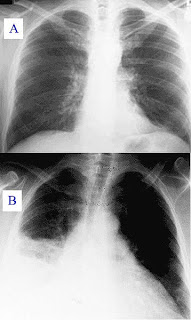

Hastalığın tanısı fiziki muayene, akciğer filmi çekilmesi, balgam kültürü yapılması ve tam kan tetkiki benzeri şekillerde konulabilir.